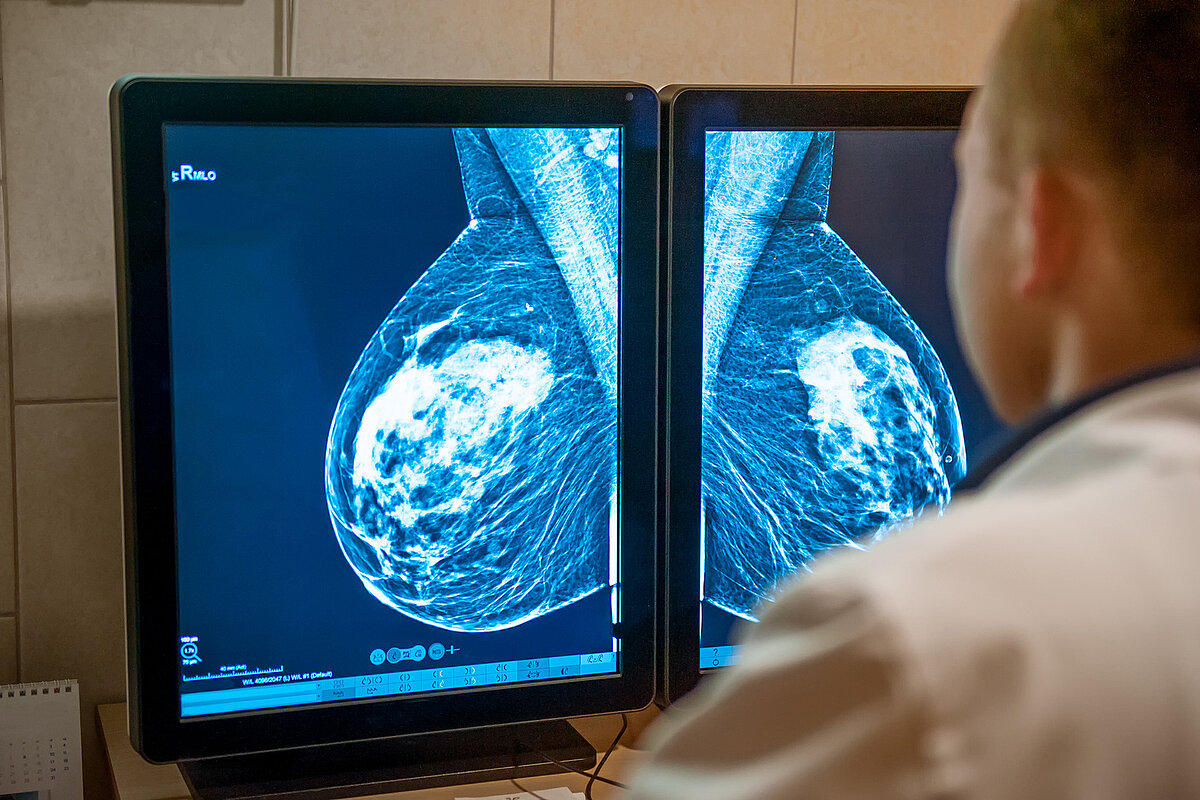

Ein Arzt sitzt vor zwei Monitoren und analysiert zwei MRT-Aufnahmen einer weiblichen Brust im Rahmen der Brustkrebs-Früherkennung.

• Foto: QuaMaDi: Brustkrebs-Früherkennung in Schleswig-Holstein

Format: JPG | 859 KB | 2200 × 1467 px

Lizenz: Dieses Bild darf nur im Zusammenhang mit der nebenstehenden redaktionellen Berichterstattung und ausschließlich von Zeitungsredaktionen bzw. Verlags-/Medienhäuser für ihre Print-Publikationen (Veröffentlichung ist auf 500k Kopien begrenzt), Online-Plattformen und für ihre sozialen Medien genutzt werden. Bitte geben Sie immer die folgende Quelle (Copyright) an: AOK NordWest/Colourbox/hfr.